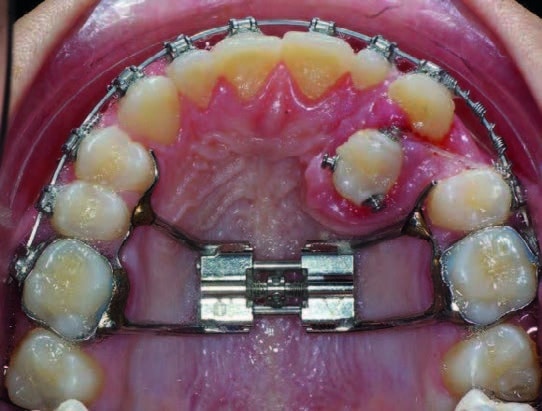

Lorsque la prémolaire est suffisamment palatine pour que la canine puisse être mésialée, un ressort en compression placé entre 25 et 23 permet de mésialer la canine. La présence du disjoncteur potentialise l’ancrage postérieur pour mésialer la canine.

En même temps, la prémolaire est tractée par une chaînette élastomérique en direction disto-vestibulaire. Un boîtier est fixé sur 24, un arc à mémoire de forme 0,020 x 0,020 termine la mise en place de la dent sur l’arcade ; (Fig.13). Le traitement n’est pas encore terminé, l’orthopantomographie de fin de traitement n’est donc pas encore réalisée ; (Fig.14).